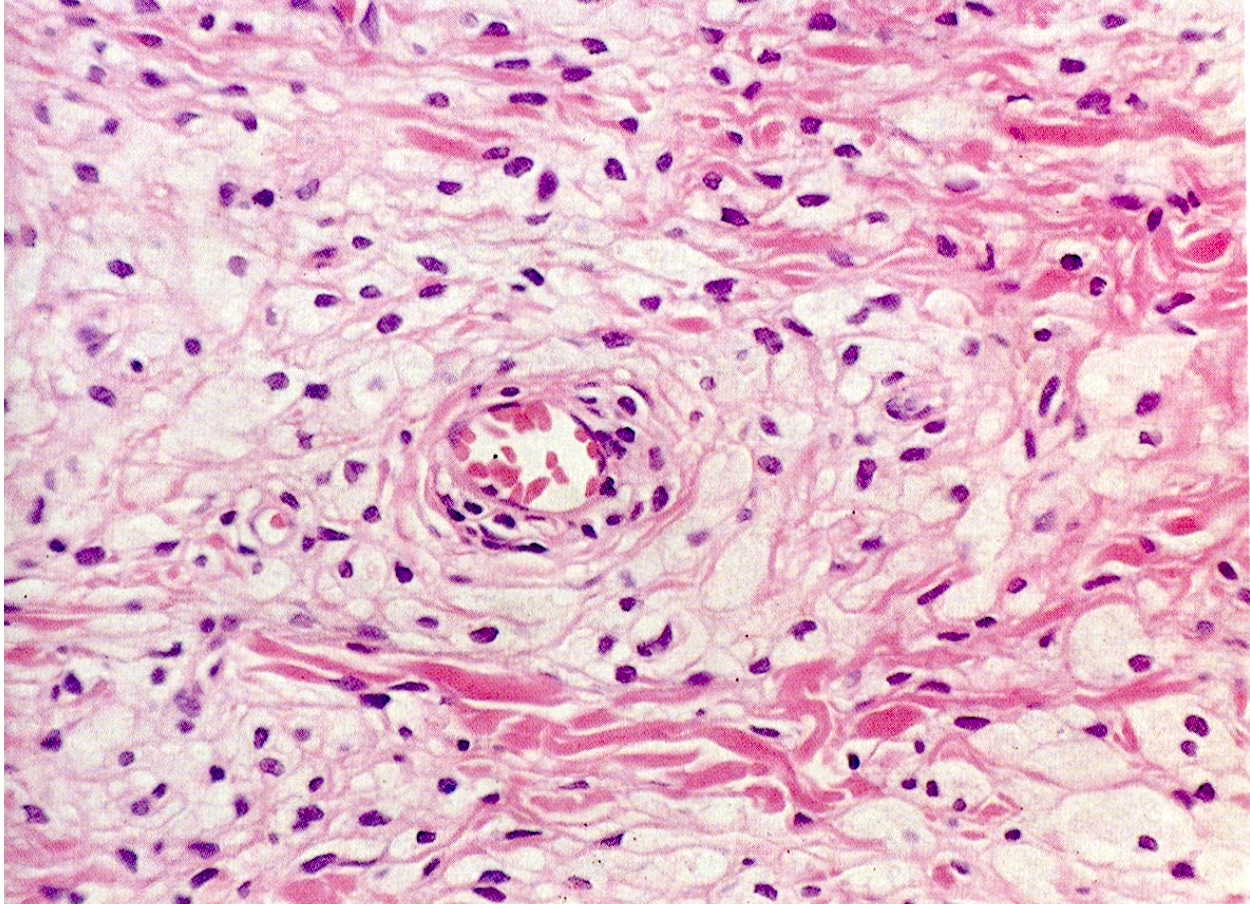

(右の写真は血管の枝に沿って白っぽい粒々に見える黄色腫が奥の方まで続いている様子を示す。)

眼瞼黄色腫の本体は、血管から染み出した脂肪やコレステロールを貪食して大きくなった組織球(マクロファージ)の大集団です。脂肪を溜め込んで顕微鏡では泡のように見えるため、泡沫細胞とも呼ばれます。血管の周りを取り巻くように集塊を形成し、線維性の結合織で囲まれて分葉状に発育していきます。ですから、その中心には常に血管があり、枝分かれした細小血管にぶどうの房のように粒々の腫瘍塊が鈴なりになっています。